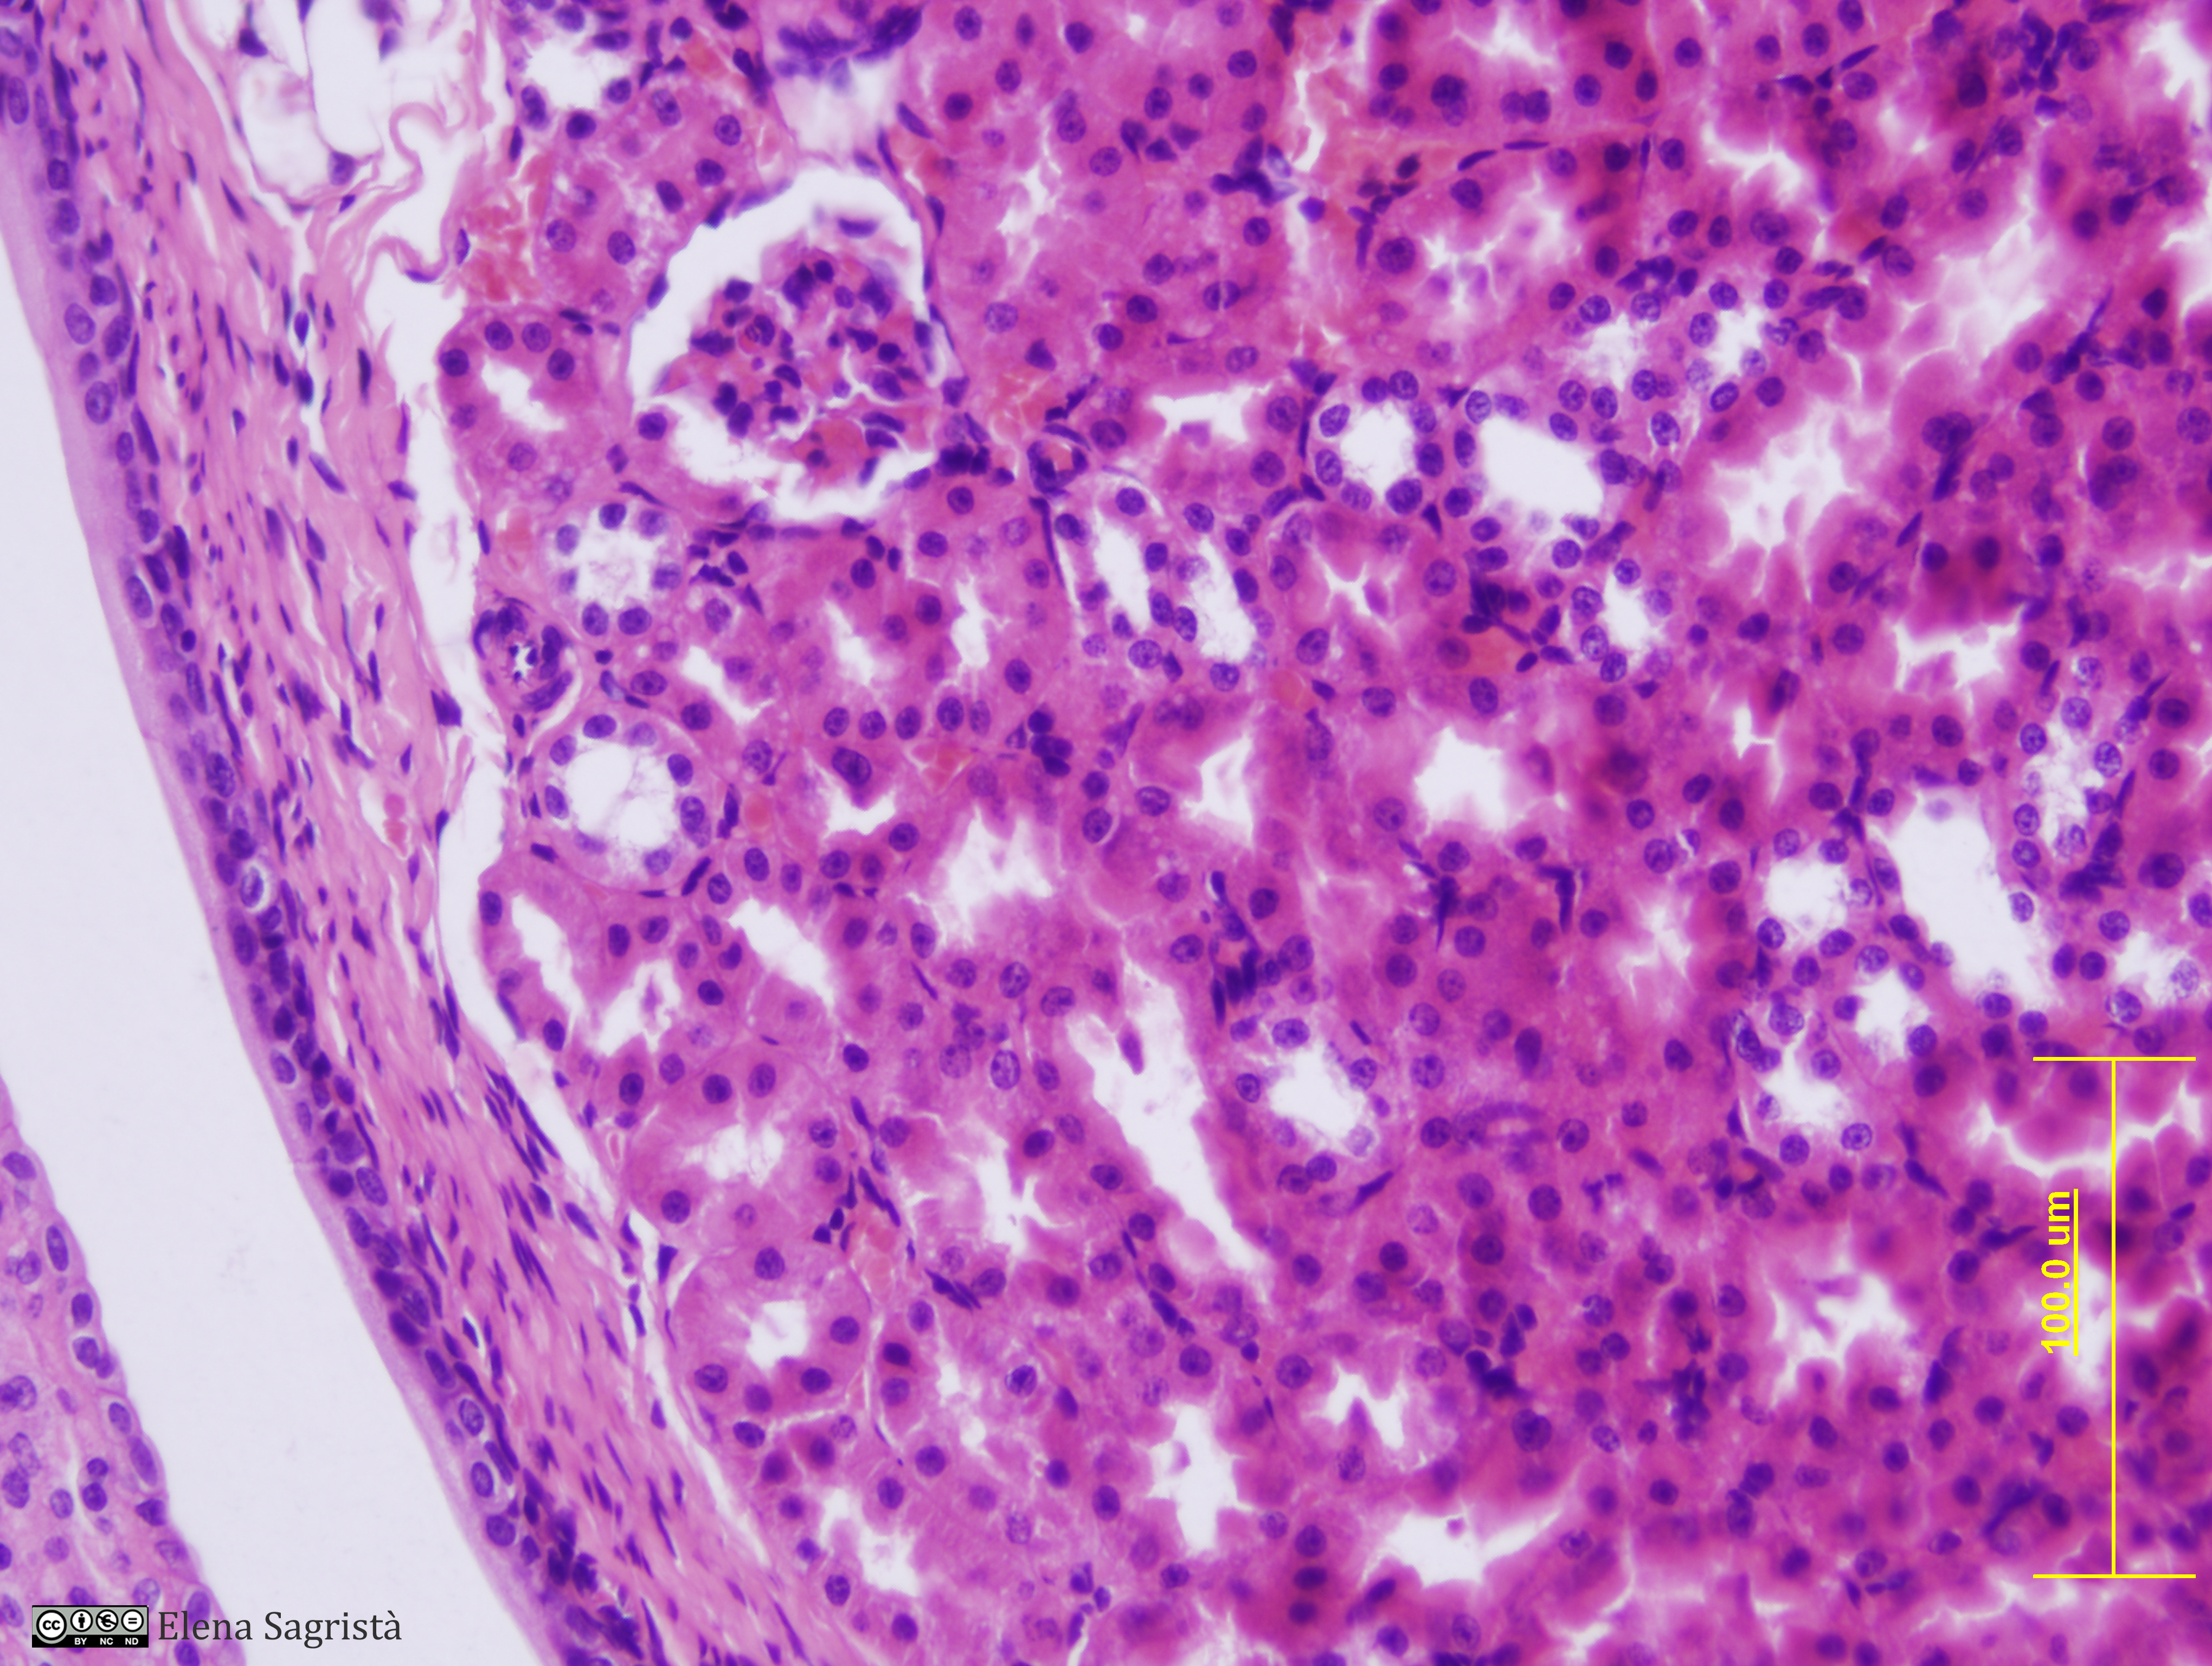

Histologia imatges: 21 Ronyò i Bufeta

Imatges de preparacions histològiques de Ronyò i Bufeta. Microscopia òptica.